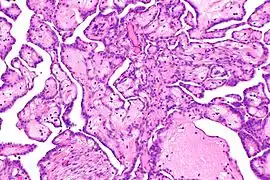

- Carcinome : la majorité des cellules cancéreuses sont d'origine épithéliale, nées dans les tissus qui enveloppent les organes.

Cellules de carcinome.